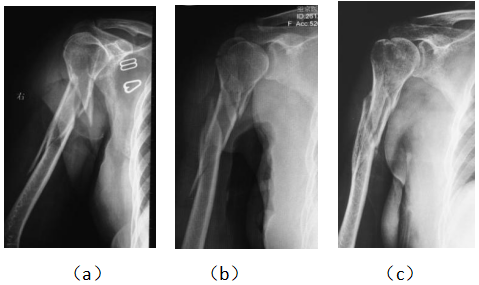

病例3,女,55岁,右侧肱骨粉碎性骨折, 用药后7周恢复。治疗前,有多处粉碎性骨折的, 成角畸形(a),小夹板垫压缩固定(b),7周后恢复(c)。

Case 3, female 55 years old, right lateral comminuted fracture of bone and shaft of 耾, recovered 7 weeks after medication. Before eating, there were multiple comminuted fractures of the bone and shaft of 耾, angular deformity (a), compression and fixation of small splint pad (b), and recovery (c) after 7 weeks.